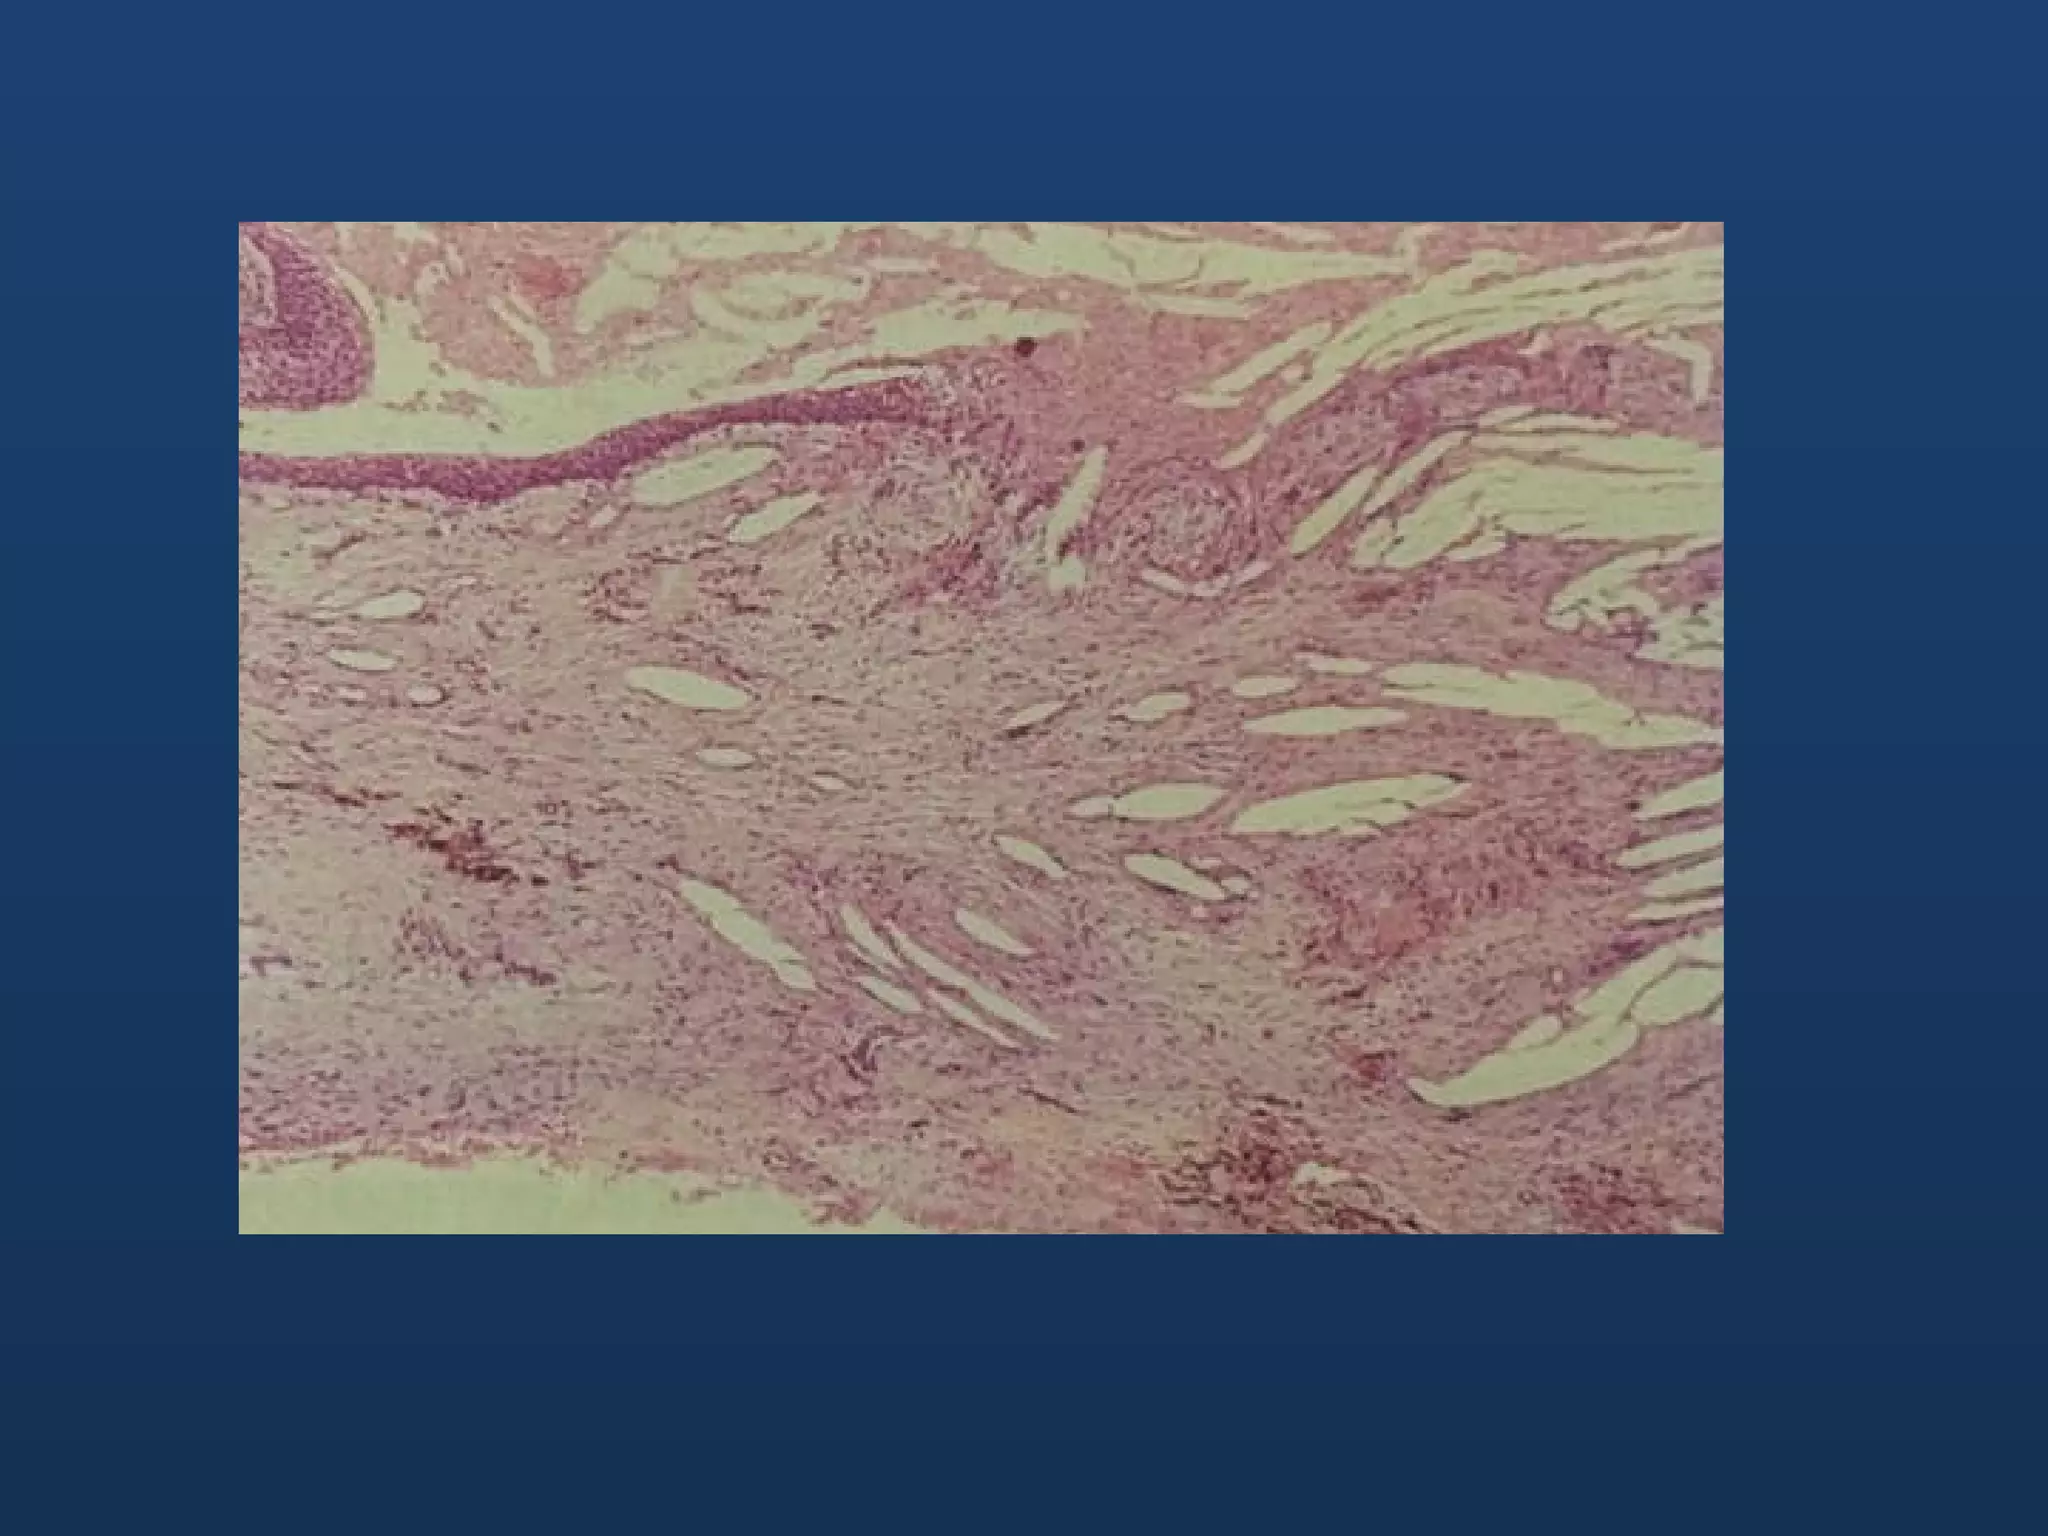

Histopathology • Lined bynon-keratinized stratified squamous epithelium • Chronically inflamed fibrous tissue capsule • Newly formed cysts have irregular epithelial lining with variable thickness. Becomes regular and even in thickness

• #8 Periapical granuloma containing proliferating arcades of squamous epithelium, showing early cystic breakdown

• #9 This is the previous section magnified, showing the early microcyst, associated with epithelial breakdown within the lesion

• #10 This is an early radicular cyst showing the long anastomosing cords of epithelium and the variation in the thickness of the epithelial lining. As the cyst grows it becomes more regular like the next slide

• #11 this is a section in an established cyst showing the thin and even epithelial lining